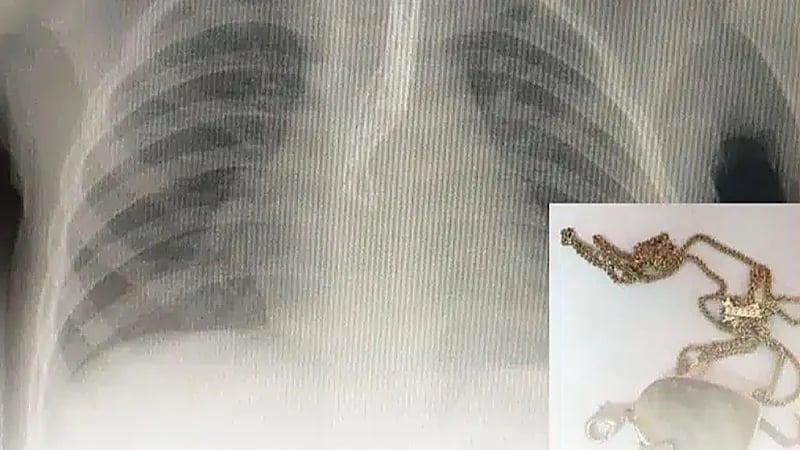

“الفرق الطبية“ تنجح في إنقاذ حياة طفلة ابتلعت “قلادة” بالمدينة المنورة